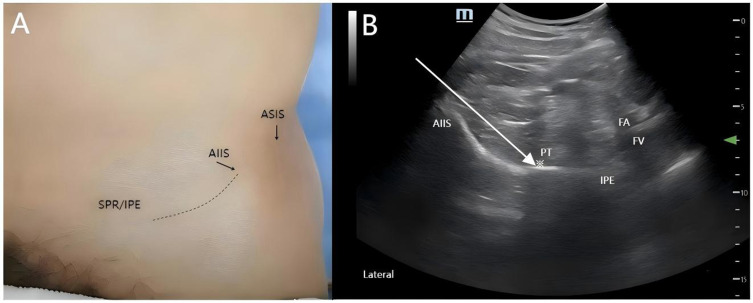

囊周神经群阻滞(PENG)是一种用于急性疼痛管理的区域麻醉技术,已成为急诊下肢骨折,特别是髋部损伤的常用麻醉方法。虽然目前的证据主要来自术后随机试验和病例系列,但最近的临床报告结果支持手术前在紧急情况下使用PENG阻滞快速镇痛40-60%的疼痛评分降低和保持运动功能。本综述综合了文献中的机制见解和临床结果,比较了髋关节囊的靶向感觉阻滞、PENG阻滞与全身性阿片类药物(有引起呼吸抑制的风险)和髂筋膜阻滞(可引起运动障碍)。彭阻断的主要优点包括显著的阿片类药物节约作用(吗啡使用减少50-70%)和几乎没有运动并发症。标准化的超声引导方案可以解决与解剖变异性相关的挑战。来自病例报告的初步证据表明,彭阻滞对骨盆和股骨干骨折有效,尽管需要多中心试验来确定最佳剂量和长期功能结果。这一证据表明,PENG阻断可以作为一种有希望的紧急干预措施,但需要进一步改进方案。

The pericapsular nerve group (PENG) block is a regional anaesthesia technique for acute pain management that is becoming frequently employed for emergency lower limb fractures, particularly hip injuries. While current evidence has been predominantly derived from postoperative randomized trials and case series, the results of recent clinical reports support the preprocedural utility of the PENG block in emergency settings for rapid analgesia 40-60% pain score reduction and preservation of motor function. This review synthesizes mechanistic insights and clinical outcomes from the literature, comparing the targeted sensory blockade of the hip capsule with the PENG block with that of systemic opioids (which risks inducing respiratory depression) and fascia iliaca block (which can induce motor impairment). Key advantages of PENG blockade include significant opioid-sparing effects (50-70% reduction morphine use) and almost no motor complications. Standardized ultrasound-guided protocols can address challenges related to anatomical variability. Preliminary evidence from case reports suggests that the efficacy of the PENG block to pelvic and femoral shaft fractures, although multicentre trials are needed to establish optimal doses and long-term functional outcomes. This evidence indicates that PENG blockade could serve as a promising emergency intervention, but further protocol refinement is warranted.